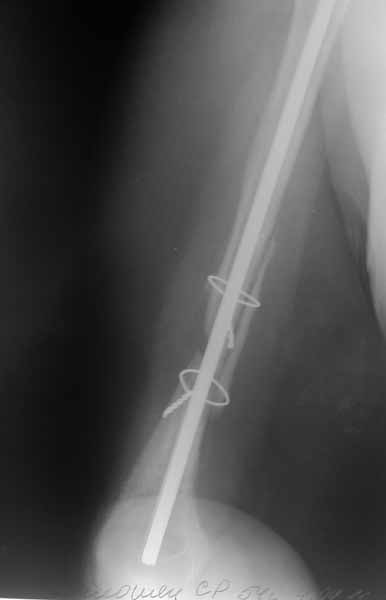

Отправитель: Молодцов Максим 29 Июнь 2011, 21:23

После БИОС

Первым этапом выполнено удаление металлоконструкции и БИОС плечевой кости с костной аутопластикой плечевой кости. Послеоперационный период без особенностей. Пациентка получила полный курс электромиостимуляции.